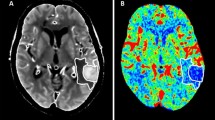

Postprocessing of raw CTP source images was performed on CT Perfusion 4D software of a standard Advantage Workstation (AW 4.7, GE Healthcare). The software performed head motion correction and generated mathematical descriptions of time-density curves for each brain voxel. Arterial input and venous output were derived from the ipsilateral anterior cerebral artery and the superior sagittal sinus. The parametric maps PS were calculated by the same software using a deconvolution algorithm. The PS value is a measure used to assess the rate of contrast leakage from the intravascular to extravascular space through a disrupted BBB. Regions of interest (ROIs) were drawn using planimetric techniques on raw CTP images and were transferred to corresponding PS maps. At the image slice with the maximum hematoma area, 8 approximately equidistant 80mm2 round ROIs were marked within the 1 cm boundary region outside the hematoma. Contralateral mirror ROIs were constructed by reflecting the ROIs around hematoma across the brain midline (Fig. 1). Mean PS values were calculated by averaging the PS values in 8 ROIs in each brain hemisphere. To minimize the impact of patient level heterogeneity, relative PS (rPS) value was calculated as a ratio of ipsilateral to contralateral mean PS. Large blood vessels, ventricles, image artifacts, bones, and calcifications were avoided while drawing the ROIs to ensure more accurate and repeatable results. This CTP post-processing was independently completed by two experienced radiologists.

Graphical illustration of the regions of interest (ROIs) drawn on computed tomography perfusion baseline image (a) and corresponding permeability-surface area product map (b). The region between two red lines defines a 10mm zone surrounding the hematoma. Yellow circles define ROIs drawn in the perihematomal region